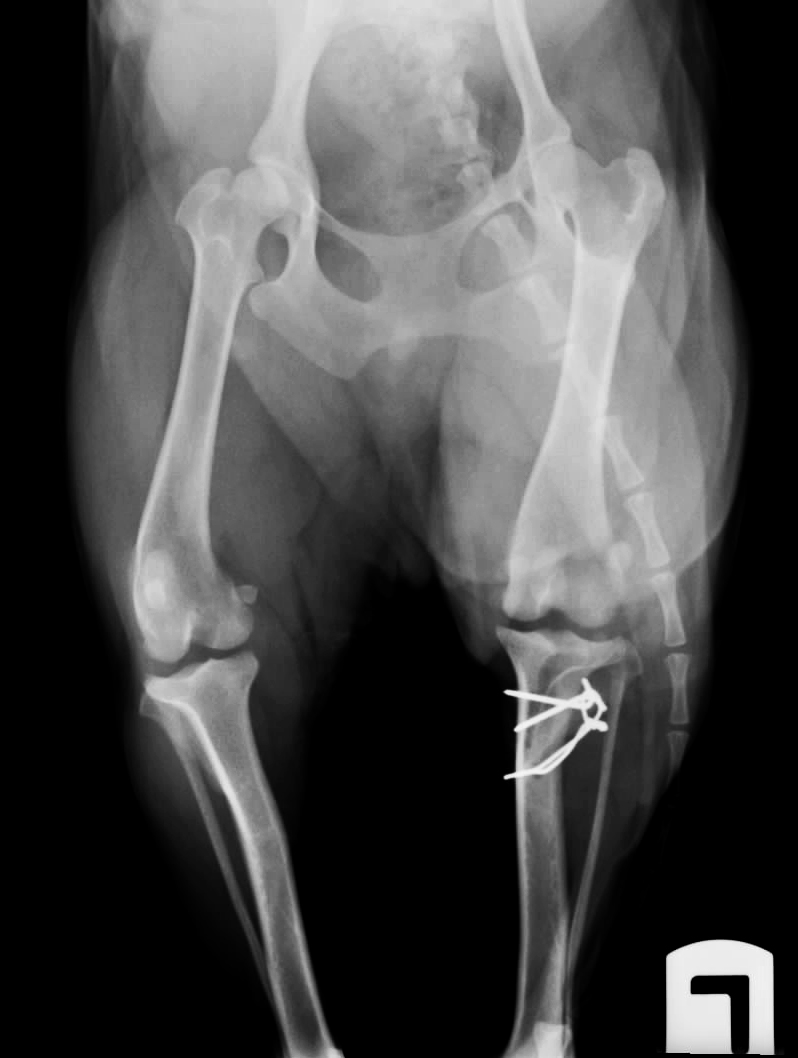

WebGrado I. Luxación de rótula intermitente, causando cojera de la extremidad solo cuando está fuera de su sitio. Son perros que cada tres o cuatro pasos levantan la. WebPara confirmar la sospecha de luxación patelar en perros, el veterinario palpará la rodilla cuidadosamente. Además, comprobará en qué medida y en qué dirección se luxa la. WebUna luxación rotuliana en perros es una de las anomalías más frecuentes de la articulación de la rodilla en los perros. La condición es más común en razas de perros de juguete y. WebEjercicios Para Luxación De Rótula En Perros Hola y gracias por visitar nuestro blog. En este artículo hablaremos de un producto de mucha calidad y muy buscado en tiendas en. WebClasificación de la luxación de rótula en perro. Existen varios sistemas de clasificación de la severidad de la luxación, pero el más usado por los clínicos es el de Roush, que.

WebUna luxación rotuliana en perros es una de las anomalías más frecuentes de la articulación de la rodilla en los perros. La condición es más común en razas de perros de juguete y. WebEjercicios Para Luxación De Rótula En Perros Hola y gracias por visitar nuestro blog. En este artículo hablaremos de un producto de mucha calidad y muy buscado en tiendas en. WebClasificación de la luxación de rótula en perro. Existen varios sistemas de clasificación de la severidad de la luxación, pero el más usado por los clínicos es el de Roush, que. WebA continuación apretaremos la pelota con ambas rodillas, intentando que las dos piernas hagan la misma fuerza. Elevar pierna inferior: nos colocaremos. WebShow more. 🦴LUXACIÓN DE RÓTULA EN PERROS Hoy os hablamos de la LUXACIÓN DE RÓTULA en perros y os contamos el caso de Lupe, esta YorkShire que padecía un. WebLa operación de luxación de rotula para perros significa conseguir que el hueso no duela al perro y pueda caminar y correr sin problemas. Se trata de la reconstrucción del hueso y. WebEn la situacion de las rodillas, existen varios ejercicios que se tienen la posibilidad de llevar a cabo, pero los más destacados son: Los paseos acuáticos asisten a recobrar la. WebLa otra rotula nunca le ha quedado al 100% y sigue casi igual de coja que antes d la operacion. Esta perra tuvo cachorros (yo no sabia que eso se heredaba) y uno de ellos. WebMasoterapia para perros con luxación de rótula. La terapia de masaje y el ejercicio correctivo pueden beneficiar a los perros con luxación leve de rótula. El.